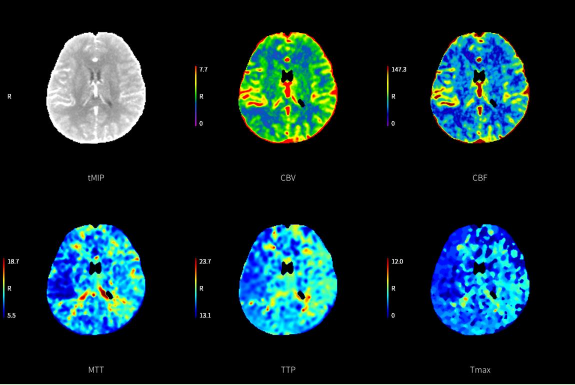

(一)腦卒中“一站式”CT檢查,包括CT平掃(NCCT),CT血管成像(CTA)和CT灌注成像(CTP),成像方法簡便,3-5分鐘即可完成檢查。只需一次檢查即可完成腦卒中治療前評估,為患者得到及時有效的治療提供有力支持。

圖片

腦卒中“一站式”CT檢查